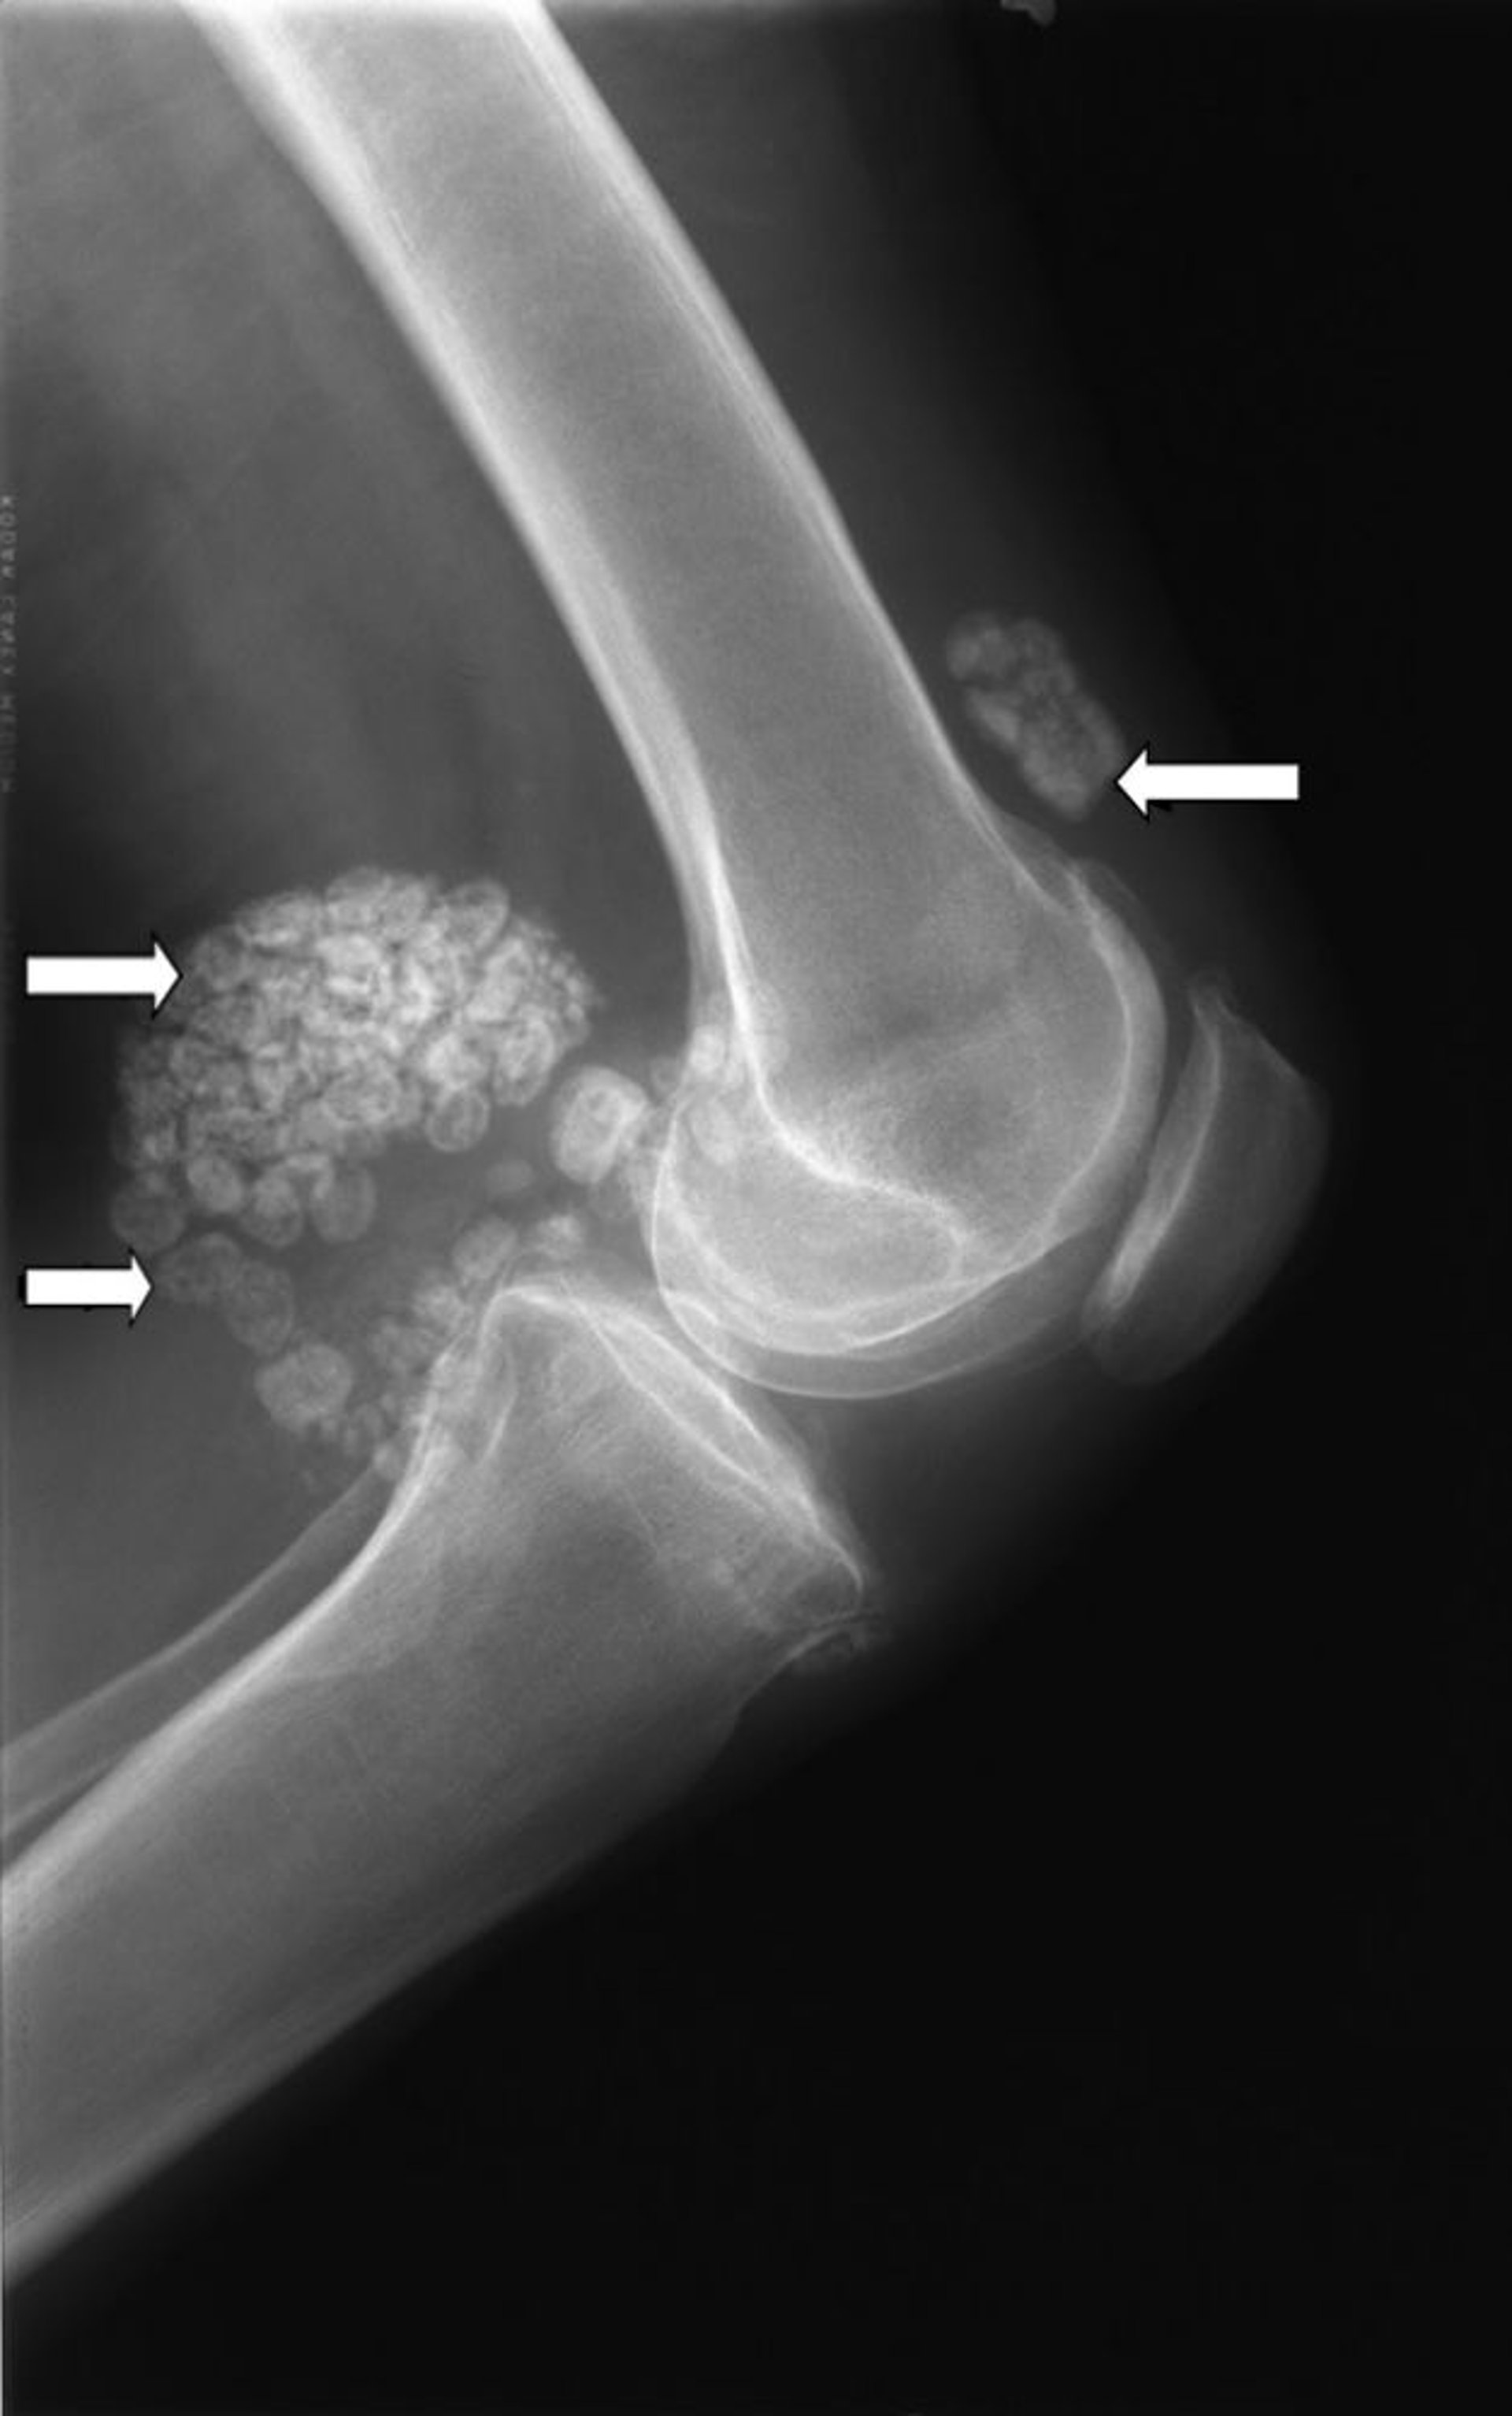

Chondromatose synoviale

Cette radiographie du genou montre plusieurs amas de cartilage (flèches), appelés chondromatose synoviale.

Image publiée avec l’aimable autorisation des Drs Michael J. Joyce et Hakan Ilaslan.